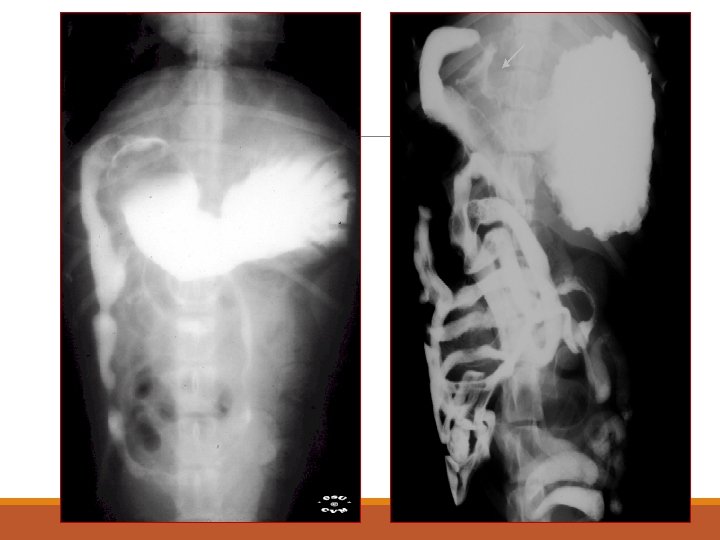

Normal Barium Swallow

Megaesophagus